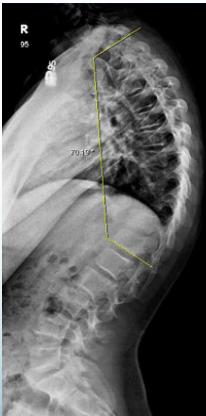

Cobb’s Angle

- Measures the amount of curve

- Angle between perpendicular lines to the uppermost and lowermost vertebral bodies in the curve

Cobb Angle Measurement

- Select most tilted vertebrae above and below curve apex

- Angle between intersecting lines drawn perpendicular to superior vertebra top and inferior vertebra bottom